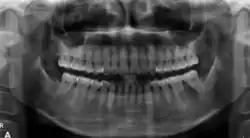

In its early stages, central ossifying fibroma (COF) appears as a small, well-defined radiolucent lesion due to its fibrous tissue content. Differential diagnoses at this stage include periapical pathology, central giant cell granuloma, and ameloblastoma.[22][23] As the lesion matures, it exhibits a mixed radiolucent-radiopaque appearance due to progressive calcification.[22] At this stage, it should be differentiated from other mixed jaw lesions such as fibrous dysplasia, calcifying epithelial odontogenic tumour, adenomatoid odontogenic tumour, and condensing osteitis.[22] In its mature form, COF may appear predominantly radiopaque, resembling lesions like odontomas, osteoblastomas, or osteosarcomas radiographically.

COF typically presents with well-defined, smooth, and often corticated borders. As a central lesion, it originates within the medullary bone and expands concentrically in all directions.[24] With growth, it may cause tooth displacement, root resorption, inferior displacement of the mandibular canal, and loss or alteration of the lamina dura of adjacent teeth.[25]

In conclusion, COF most commonly occurs in the mandible and expands from a central epicenter. Radiographically, it presents as a well-defined mixed-density lesion,[26] and Cone Beam CT (CBCT) plays a crucial role in its accurate diagnosis and assessment.